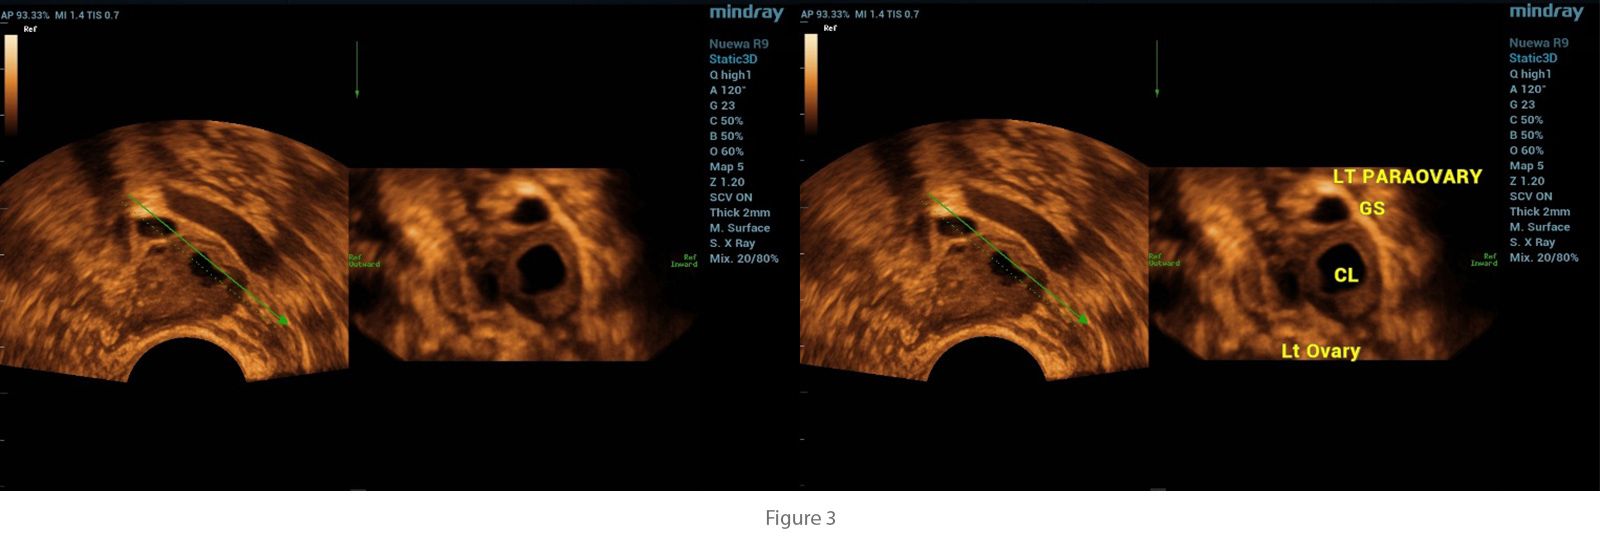

All ultrasound examinations were performed using the Nuewa R9 Ultrasound System (Mindray, Shenzhen, China). A convex transducer (SC6-1U) was employed for general pelvic evaluation, and a 4D transvaginal transducer (DE11-3WU) was used for detailed assessment of the uterus and adnexa. Imaging modalities included two-dimensional (2D) grayscale ultrasound, Color Doppler, and four-dimensional (4D) imaging.

To enhance diagnostic accuracy, advanced imaging applications were applied. Smart Endometrial Receptivity Analysis (Smart ERA) was utilized to assess endometrial morphology and volume, while the SCV+ function was employed to improve spatial resolution and delineation of adnexal structures. These features contributed to the precise characterization of the ectopic gestational sac and detailed evaluation of ovarian and endometrial parameters.

In this case, transvaginal ultrasound was central to the diagnosis. The examination revealed the absence of an intrauterine gestational sac despite a positive pregnancy test, a finding highly suggestive of ectopic pregnancy. Additionally, a small gestational sac was visualized outside the uterine cavity, confirming the diagnosis. These ultrasound findings, when correlated with the patientŌĆÖs symptoms of abdominal pain and vaginal spotting, highlight the critical role of transvaginal imaging in detecting ectopic pregnancies at an early stage, enabling prompt intervention and reducing the risk of complications.